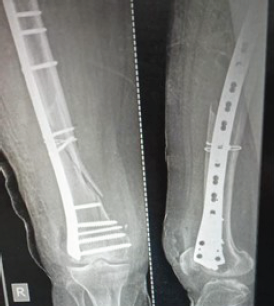

Role of Distal Femur Anatomical Plate in Fracture of Distal Femur

Aliasgar Rampurwala , Mitul Modi , Akshay Chhatrola , Arvind Kumar

………………………………p.231-236